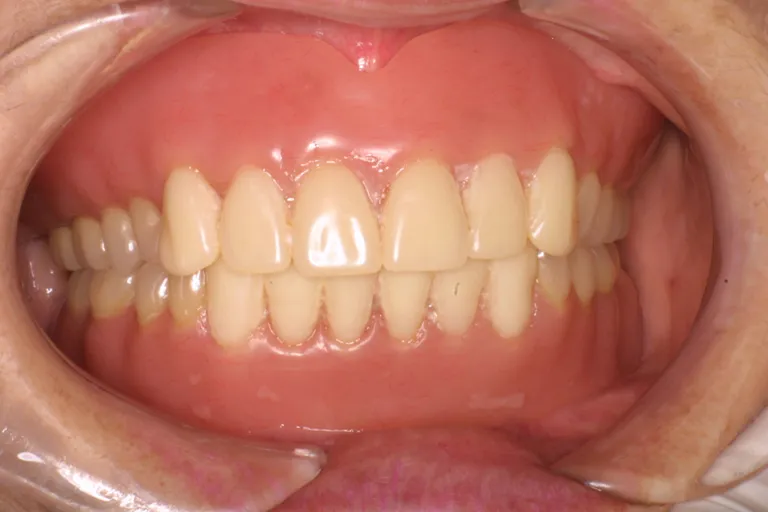

■術前の状態■多くの治療跡があり上顎は大半の歯が失われています総合的に見直して治療する必要があります

■術前の状態■

多くの

治療跡があり

状態が悪い

■術後の状態■インプラント・メタルボンド・アタッチメント義歯を含む包括的治療の例です

■術後の状態■

様々な治療法を

用いた

包括的治療の一例

■術後の状態■しっかりと噛める強度と快適な装着感で外からは自然な見た目です

しっかり噛める

口腔環境にします